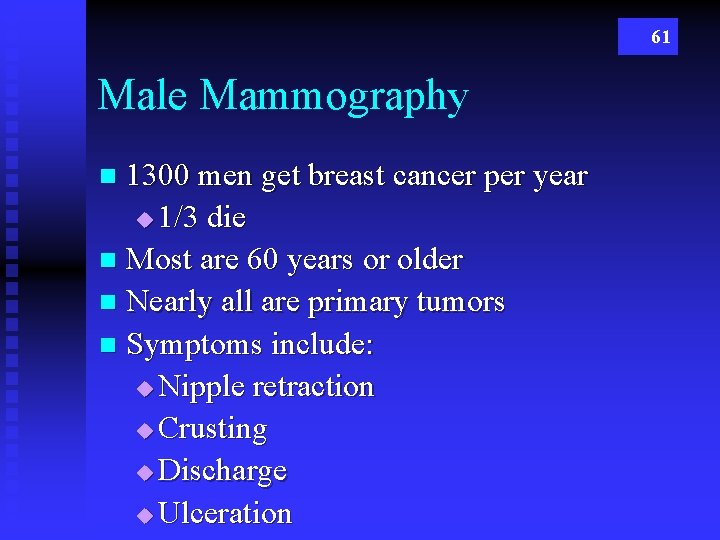

61 Male Mammography 1300 men get breast cancer per year u 1/3 die n Most are 60 years or older n Nearly all are primary tumors n Symptoms include: u Nipple retraction u Crusting u Discharge u Ulceration n